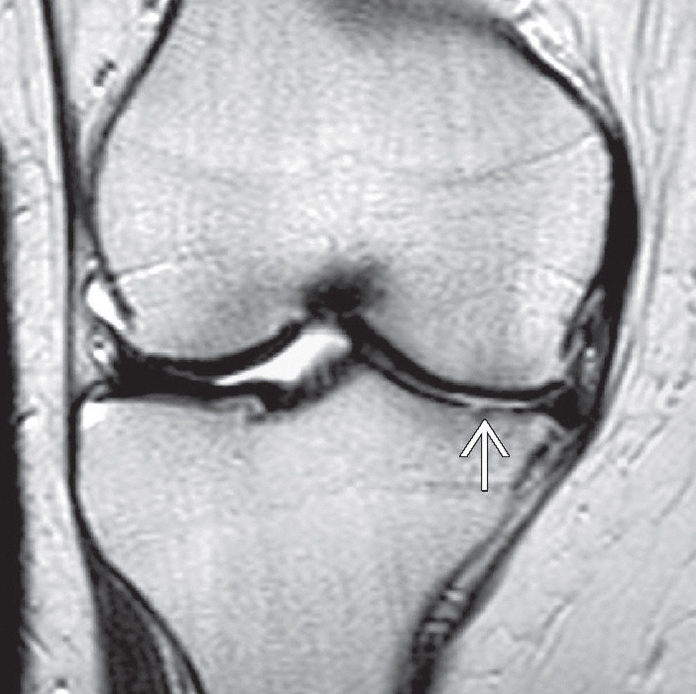

Artritik kıkırdağın görünümü

Ameliyat öncesinde hastanın şikayeti ve hikayesi dinlenir. Muayenede diz hareketleri, stabilite ve dizin gücü değerlendirilir. Ameliyat planlaması için röntgen filmleri çekilmelidir. Bazen dizdeki kemik ve yumuşak dokuların durumunu belirlemek için kan testleri veya manyetik rezonans görüntüleme (MRI) taraması gibi ileri görüntülemeler gerekebilir.

Dizin iç kısmında kıkırdak incelmiş ve buna bağlı olarak eklem aralığı daralmış.